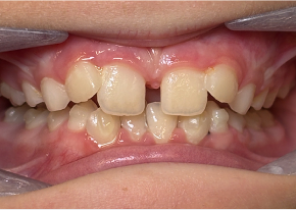

Opis przypadku nr 1

10 lat, 0 miesięcy, 18 etapów leczenia Invisalign Palatal Expander

Dzięki uprzejmości dr Sandry Khong Tai

Przed ekspansją eInvisalign Palatal Expander

Po ekspansji Invisalign Palatal Expander

Po leczeniu Invisalign First